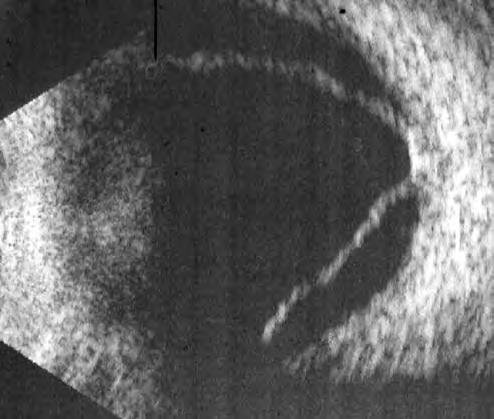

放上前置镜,我之前的想法得到印证:灰白色的视网膜隆起,漂浮在玻璃体腔里,下方可以看到一个大裂孔,裂孔边缘已经翻转,有了增值条索。

这是一个孔源性视网膜脱离的病人,且脱离的时间已经非常久,他的白内障、低眼压、葡萄膜炎表现都与陈旧性视网膜脱离相关。对于视网膜脱离的患者来说,如果不能早发现早治疗,视网膜脱离时间太长,视网膜将会丧失功能,预后会很差。